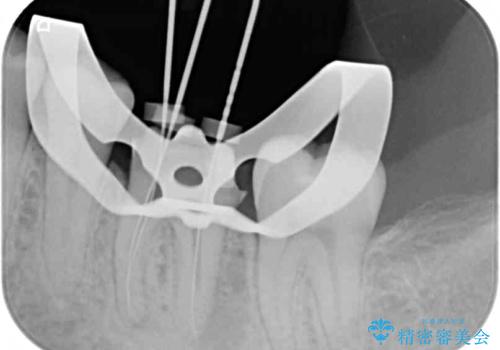

診査の結果、既に歯の神経は失活していたおり、排膿路が認められ、叩いたり触ったりしたときの痛みも確認されました。

根管治療を行った後にオールセラミッククラウンにて補綴することとしました。

初回の治療後には歯肉に認められた排膿の出口などの症状は消えていました。

補綴後6ヶ月経過しレントゲンを撮影したところ、遠心の歯根付近の病変が消失していることが確認できました。